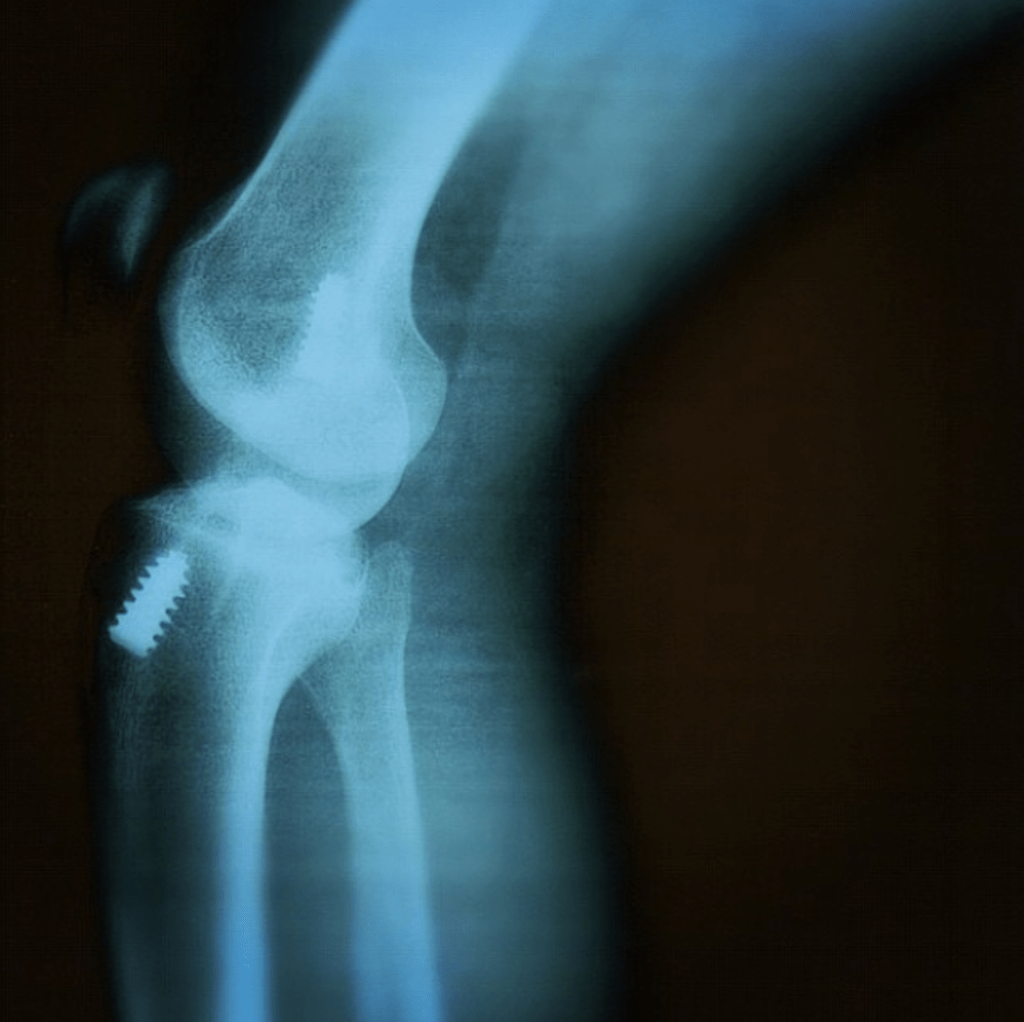

I tried to finish the game but couldn’t; I hoped the problem was something minor but it wasn’t. Week after week doctor followed by another, x-rays, and MRI, and finally the dreadful news was official: I had torn my Anterior Cruciate Ligament. I was 16 years old, and surgery was not possible due to the technique being available at the time, which meant I had to wait at least three years.

On Tuesday, September 4, 2001, I had my first ever knee surgery, which was followed by two right knee injuries due to my bad luck in sports and a lack of understanding that following the surgery, a living style should have been altered to cope with the body condition. On October 4, 2004 I had my second surgery and first right knee in Stockholm under the supervision of professor Ejnar Eriksson, and on June 6th 2017, I had my third and second right knee surgery with Dr Wael Alrayes in Kuwait.